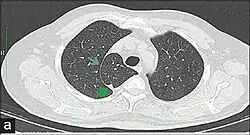

In human anatomy, an azygos lobe is a normal anatomical variation of the upper lobe of the right lung.[1] It is seen in 0.3% of the population.[2] Embryologically, it arises from an anomalous lateral course of the azygos vein,[3] in a pleural septum within the apical segment of the right upper lobe or in other words an azygos lobe is formed when the right posterior cardinal vein, one of the precursors of the azygos vein, fails to migrate over the apex of the lung and penetrates it instead, carrying along two pleural layers as the azygous fissure, that invaginates into the upper portion of the right upper lobe.[1]

An azygos lobe is usually an incidental finding on chest x-ray or CT scan. It is asymptomatic and not associated with any morbidity.[4][5] However, it can cause technical problems in thoracoscopic procedures.[6] The presence of the azygos lobe could alter the normal location of the superior vena cava or may be associated with other anomalies, including esophageal atresia or intrapulmonary right brachiocephalic veins.[7]